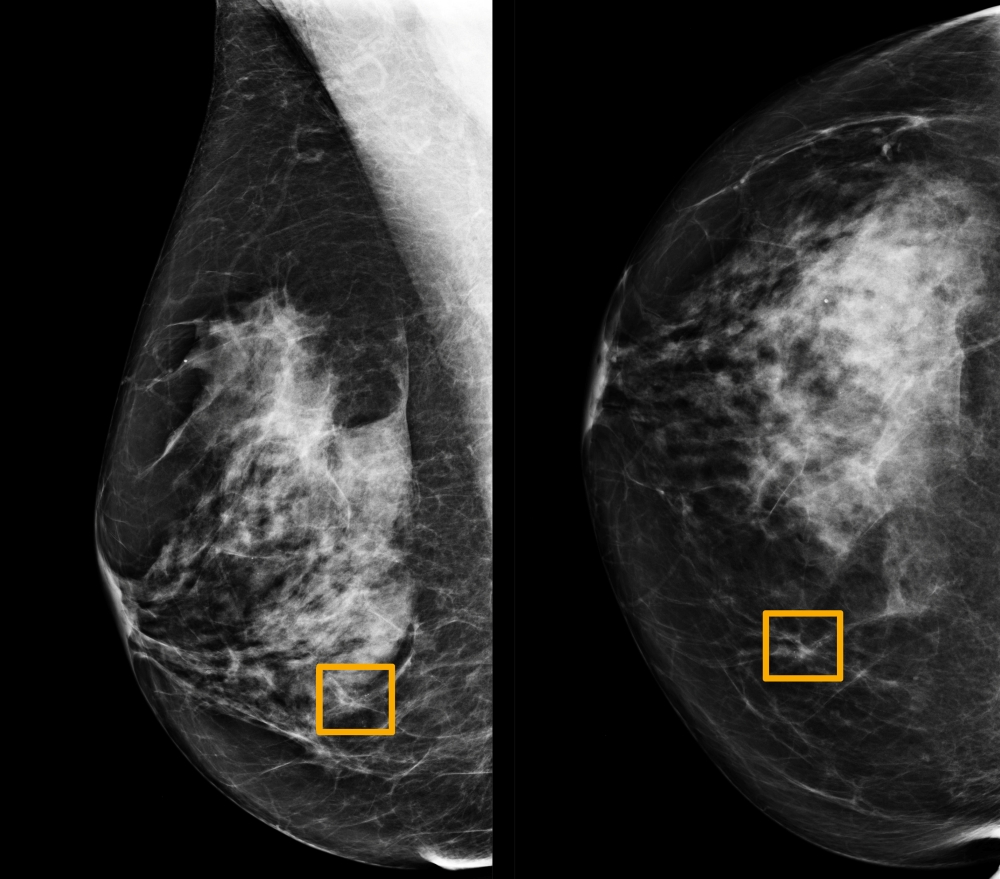

A yellow box indicates where an artificial intelligence (AI) system found cancer hiding inside breast tissue, in an undated photo released by Northwestern University in Chicago January 1, 2020. Northwestern University/Handout via Reuters